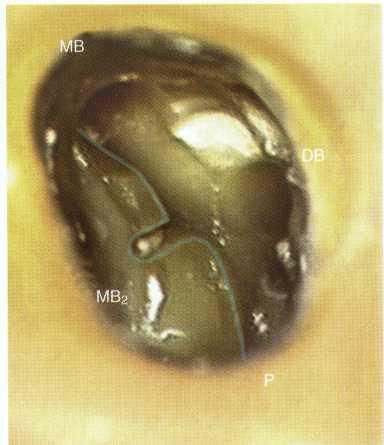

Treatment of maxillary molars is never routine (Figure 2-22). In a recent study of maxillary first and second molars an MB2 canal was found in 96% of the mesiobuccal roots of maxillary first molars and 94% of the maxillary second molars. Approximately 54% were located in the traditional access opening, 31% were found with the use of a bur, and 10% were found with the aid of a microscope. The MBZ canal orifice was found on average 1.82 mm lingual to the main MB canal orifice.9 In another study of the maxillary first molar using microscopy, the MB Z canal was located in

93% of first molars and 60% of second molars4 (Figures 2-23 and 2-24). The difficulty in access, high percentage of fourth and even fifth canals, and root curvatures put even the "routine" maxillary molar in a high-risk category.3 Complicating factors such as limited opening, crowns, changes in tooth angulation, tooth position, and calcification make predictable treatment of these teeth challenging for even the most experienced clinician trained in microscopy, ultrasonics, and rotary instrumentation.

FIGURE 2-24 The location of the MB 2 canal is mesial to the line connecting the MB and palatal orifice. In the maxillary first molar the MB2 canal is generally located within the range shown. In the maxillary second molar the location of the MB 2 s highly variable and can be located from the MB orifice to the palatal orifice (see Figs. 2-46 and 2-47).

Guidelines for canal location in the maxillary first molar (Figure 2-25) differ from that in the maxillary second molar. In the maxillary first molar the MB canal is located under the mesial buccal cusp (see Figure 2-25, D). The MBZ canal is located mesial to a line from the

MB canal toward the palatal canal (see Figures 2-25, E, and 2-26). The DB canal is located distal to the MB canal in the buccal groove area, slightly lingual to the MB canal (see Figure 2-25, G). The palatal canal is generally the largest canal and is located under the mesiolingual (ML) cusp (see Figure 2-25, F). These general locations remain the same as the pulp calcifies with age (Figure 2-27). Although these general principles apply to the maxillary second molar, the chamber may be narrower, resembling a straight line (see Fig. 2-55).

FIGURE 2-26 A, On entering the pulp chamber in this maxillary second molar, the clinician can readily locate the MB2 orifice along a line connecting the MB and palatal orifices.This "false orifice" is a source of frustration for many dentists because although it can be probed, it is often resistant to negotiation.The reason for this is that the MB 2 canal proceeds mesially (horizontally) before making a 90-degree turn down the root. B, The prepared and obturated MB 2 canal is considerably more mesial than the original orifice. The red dot to the distal of the obturated MB2 is the location of the false original orifice. A technique routinely employed is to notch this area with a tapered roundtipped diamond, Mueller bur, or Gates Glidden bur to gain straight line access to the MB 2 canal.This technique is detailed in later figures.